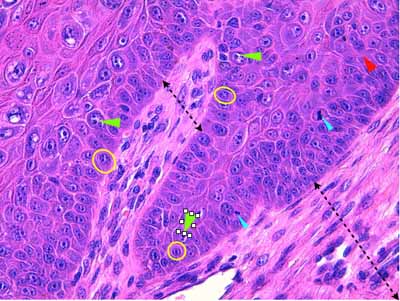

Photo 7 (Hémalun-Eosine 400) : Vue au fort grossissement du sommet

d’une papille épidermique : présence de koïlocytes : kératinocytes dont le noyau,

parfois pycnotique, est entouré d’un halo clair ou d’espaces vacuolaires.

Légendes de la Photo 7 :

- Pointes de flèche vertes : noyaux pycnotiques

- Pointes de flèche rouges : noyaux à chromatine marginée et centre basophile compatible avec une inclusion intra-nucléaire

- Pointes de flèche turquoises : volumineux et nombreux grains de kératohyaline (hypergranulose)

- Pointe de flèche jaune : corps apoptotique

- Pointe de flèche bleue : lymphocyte satellite (satellitose)

- Cercles jaunes : koïlocytes : kératinocytes dont le noyau peut être pycnotique ou à chromatine marginée et entouré d’un halo clair ou de vacuoles cytoplasmiques